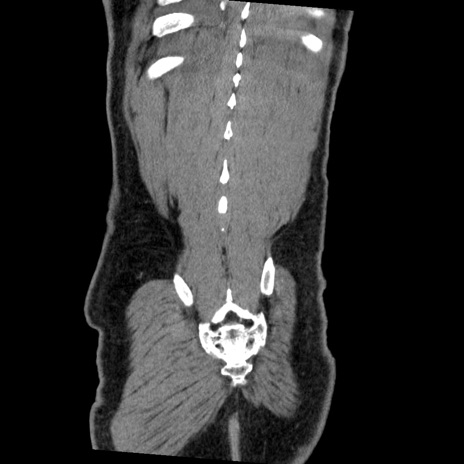

症例22(冠状断像)

【症例】50歳代男性

【主訴】腹痛

【現病歴】AVMからの被殻出血のため回復期リハ病棟入院中。 本日午後3時頃急に下腹部痛が出現した。

【既往歴】AVM、被殻出血、虫垂炎、高血圧

【身体所見】意識晴明、左半身不全麻痺、会話の理解は良好、36.5°C、腹部:膨隆、全体に板状硬、下腹部正中に圧痛点あり、反跳痛-、筋性防御不明、右下腹部にope scar

【データ】WBC 9400、CRP 0.06